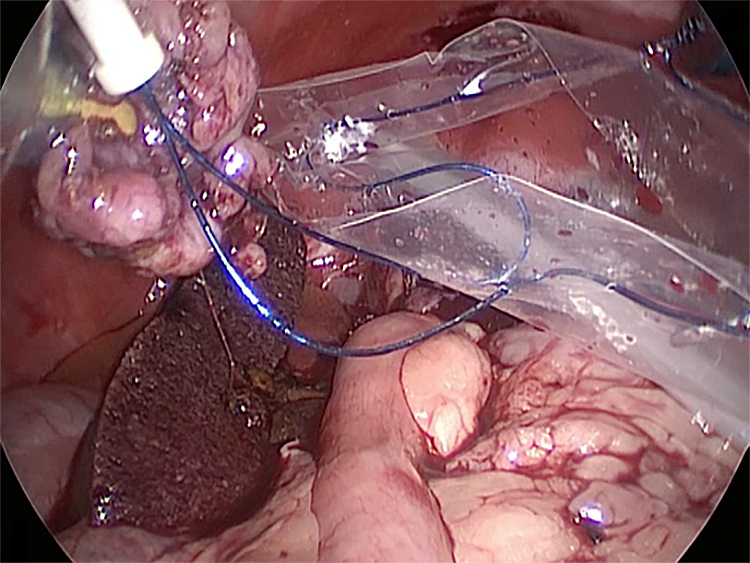

体の外に出すためお腹の中で袋に入れていきます。

このときに胆嚢と一緒にクリップやガーゼも回収します。そしてお腹の中をきれいにしていきます。

最後にお腹の中をきれいに洗浄していきます。

回収袋にいれて体外に摘出していきます。

お腹の中を洗浄して終了となります。